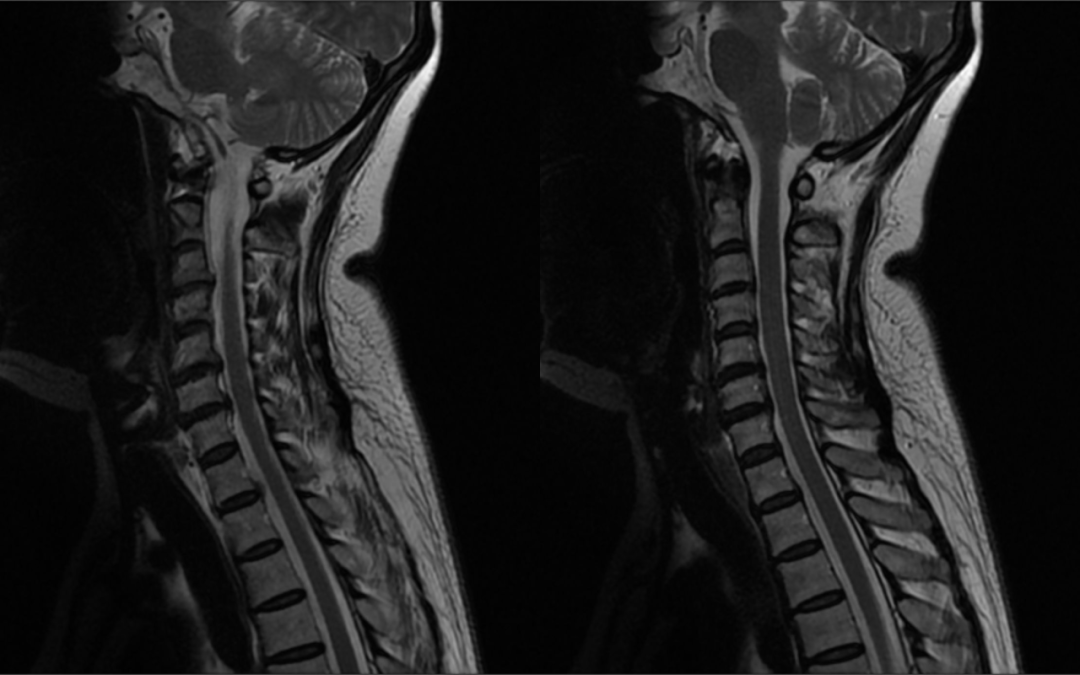

图片

颈椎MR平扫:生理曲度变直,椎体边缘骨质增生,颈3/4-6/7椎间盘向后方突出,硬膜囊受压。影像诊断为:1.颈椎退行性变;2.颈3/4-5/6椎间盘突出(中央型),颈6/7椎间盘突出(右旁中央型)。